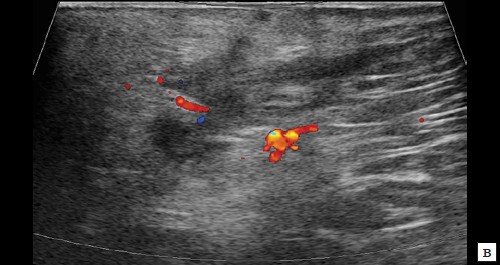

При контрольном исследовании через 3 дня после оперативного вмешательства: описываемое гипоэхогенное жидкостное образование с четкими неровными контурами с наличием неоднородного гиперэхогенного подвижного содержимого уменьшилось в размере до 2,4×1,7×1,8 см и объеме до 3,84 мл (рис. 2, а, б). В подкожно-жировой клетчатке по периферии гипоэхогенного образования отмечается уменьшение степени выраженности сосудистой реакции (рис. 2, в). Описываемый свищевой ход уменьшился в размере до 1,1×0,2×0,5 см (рис. 2, г).

в – режим ЦДК. Через 3 дня после оперативного вмешательства. В подкожно-жировой клетчатке по периферии гипоэхогенного образования отмечается уменьшение степени выраженности сосудистой реакции;